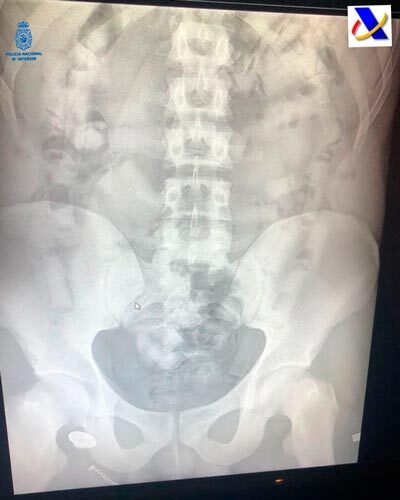

Con motivo de un control en uno de los vuelos llegado de Sudamérica fue detenido un varón del que los policías sospecharon pudiera ser portador de sustancias estupefacientes como "mulero" (persona que se introduce en su interior ese tipo de sustancias para una vez salvados los controles preceptivos defecarla y entregarla a su destinatario).

Solicitada la colaboración del servicio de vigilancia aduanera aeroportuario y su sistema de rayos x se pudo confirmar la sospecha anterior. Una vez detenido el viajero e ingresado en el hospital fue expulsando hasta un total de 50 cilindros conteniendo al parecer cocaína, resultando un total de cerca de 400 gramos.